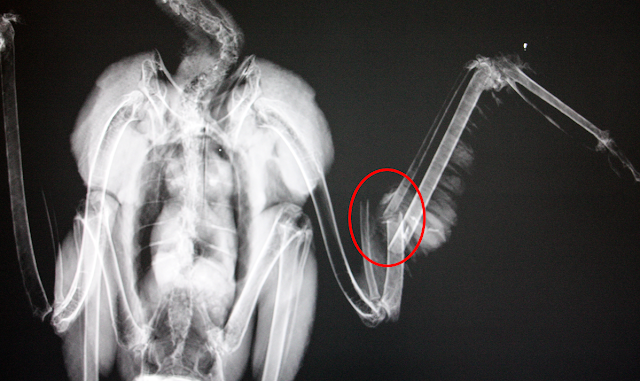

Após realizado o Raio-X, foi visível a gravidade da fratura. Desta forma, a melhor opção, que permitisse à ave voltar a voar, seria a intervenção cirúrgica.

Durante a cirurgia, a nossa veterinária inseriu cavilhas intramedulares no interior dos ossos para fazer o alinhamento destes. Mais tarde, estas cavilhas serão retiradas para permitir um uso normal da asa afetada.